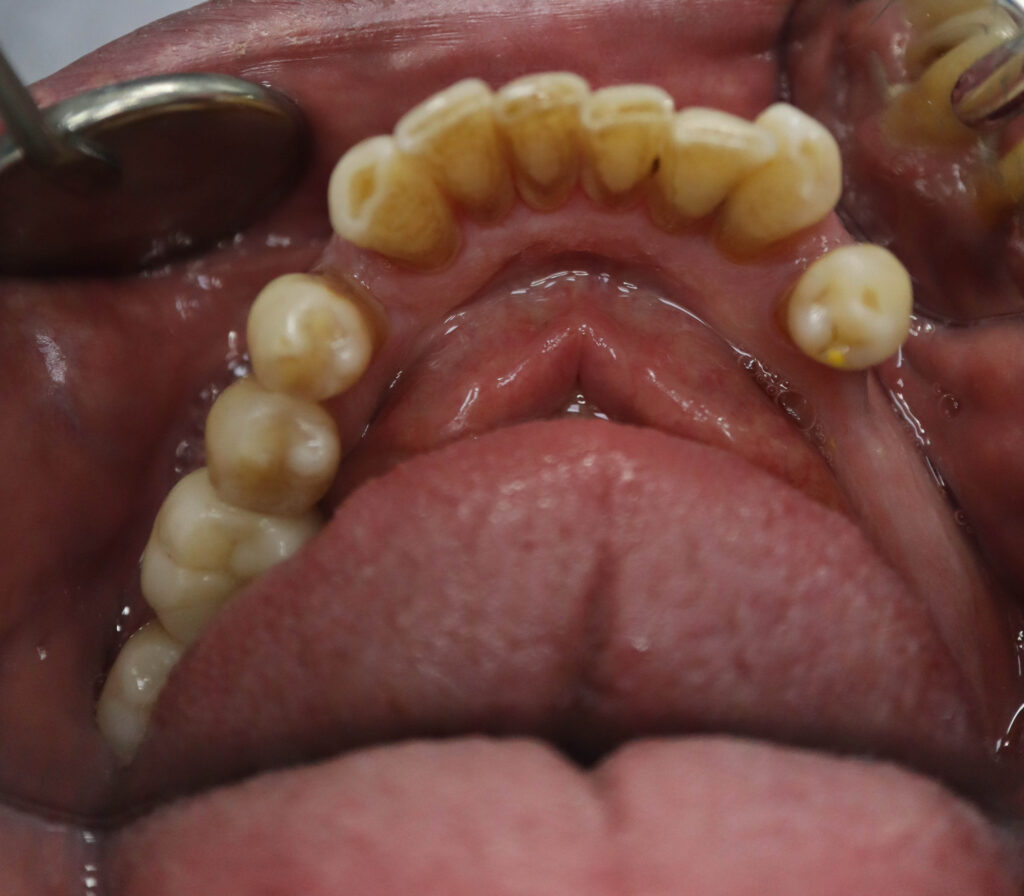

Ситуация до лечения

Пациент обратился с жалобами на эстетические недостатки.

У пациента уже стояло некоторое количество имплантатов. Было решено использовать их при протезировании.

пациент до имплантации